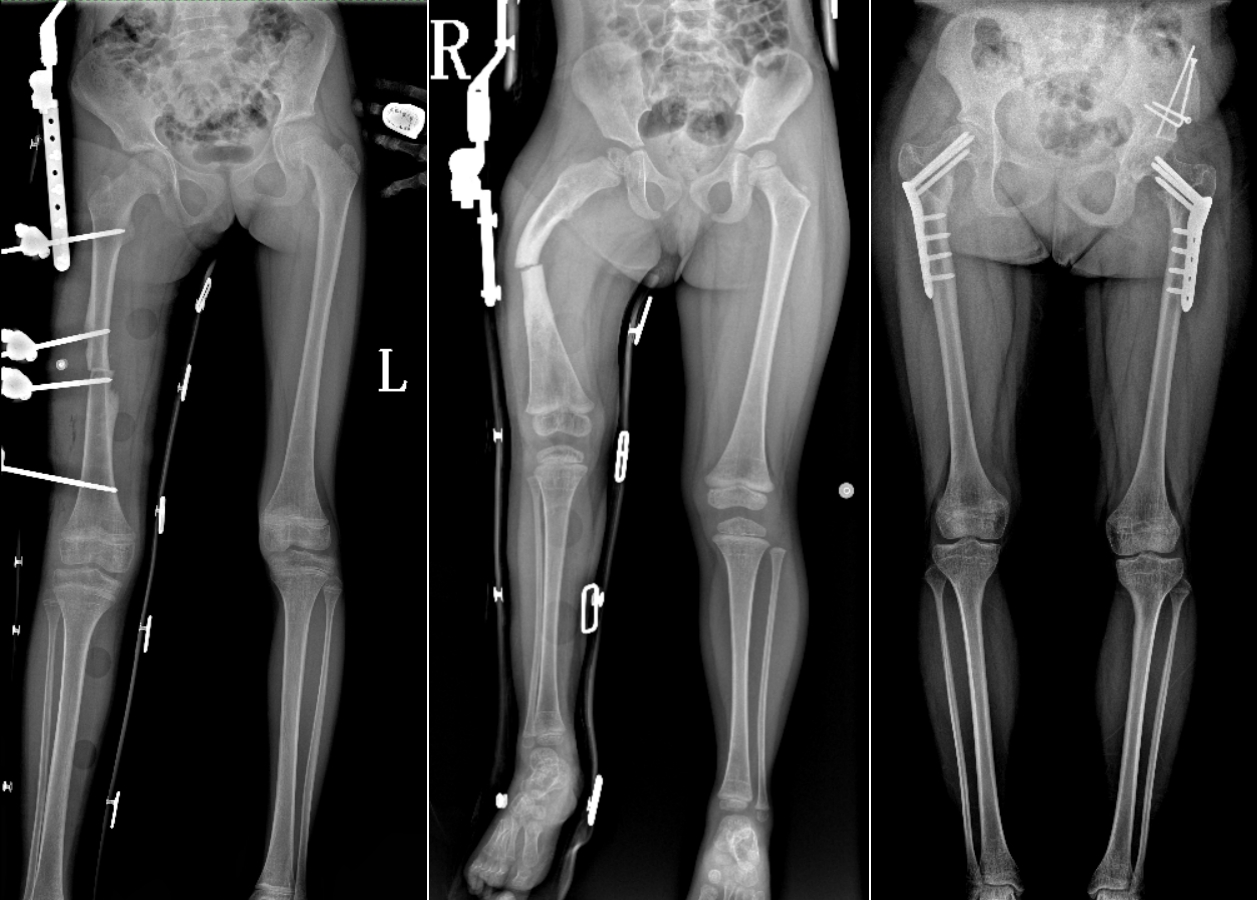

DR是臨床骨科的重要檢查手段之一。在骨科檢查中,脊柱矯形、長(zhǎng)骨骨折、腰椎退行性病變等,需要采集脊柱、下肢全景圖像,輔助醫(yī)生臨床診斷,從而制定科學(xué)的治療方案,普愛醫(yī)療的大視野平板動(dòng)態(tài)DR就像是一座橋梁,連接起現(xiàn)代醫(yī)療技術(shù)與當(dāng)?shù)厝嗣竦尼t(yī)療需求。

普愛醫(yī)療自主研發(fā)的大視野平板動(dòng)態(tài),采用17"*34"的有效視野,一次曝光即可得到全脊柱或全下肢影像。相較于多張攝影再軟件拼接的DR設(shè)備,PLX8600解決了拼接圖像存在密度不均勻,拼接處圖像配準(zhǔn)和放大效應(yīng)等問題,給臨床帶來了真正的大視野影像解決方案。

除了常規(guī)靜態(tài)攝影外,PLX8600的大平板具備動(dòng)態(tài)透視和點(diǎn)片功能,能夠很好地觀察復(fù)雜部位病灶,有效地抓取關(guān)鍵幀,降低患者多次攝片的概率。如:全脊柱狀態(tài)評(píng)估、長(zhǎng)骨關(guān)節(jié)活動(dòng)度、下肢靜脈造影瓣膜功能評(píng)估、消化道功能評(píng)估、脊髓造影等更多大視野臨床應(yīng)用,“多面手”都能輕松應(yīng)對(duì)。